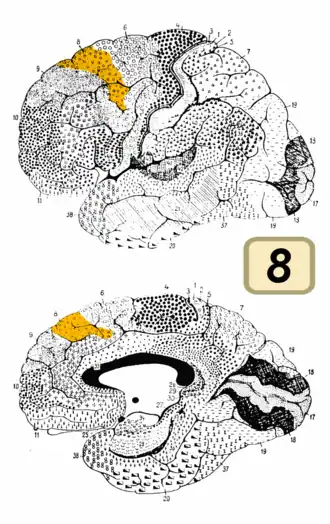

Image of brain with Brodmann area 8 shown in orange | |

Lateral view.

Lateral view. -

Medial view.

Medial view.